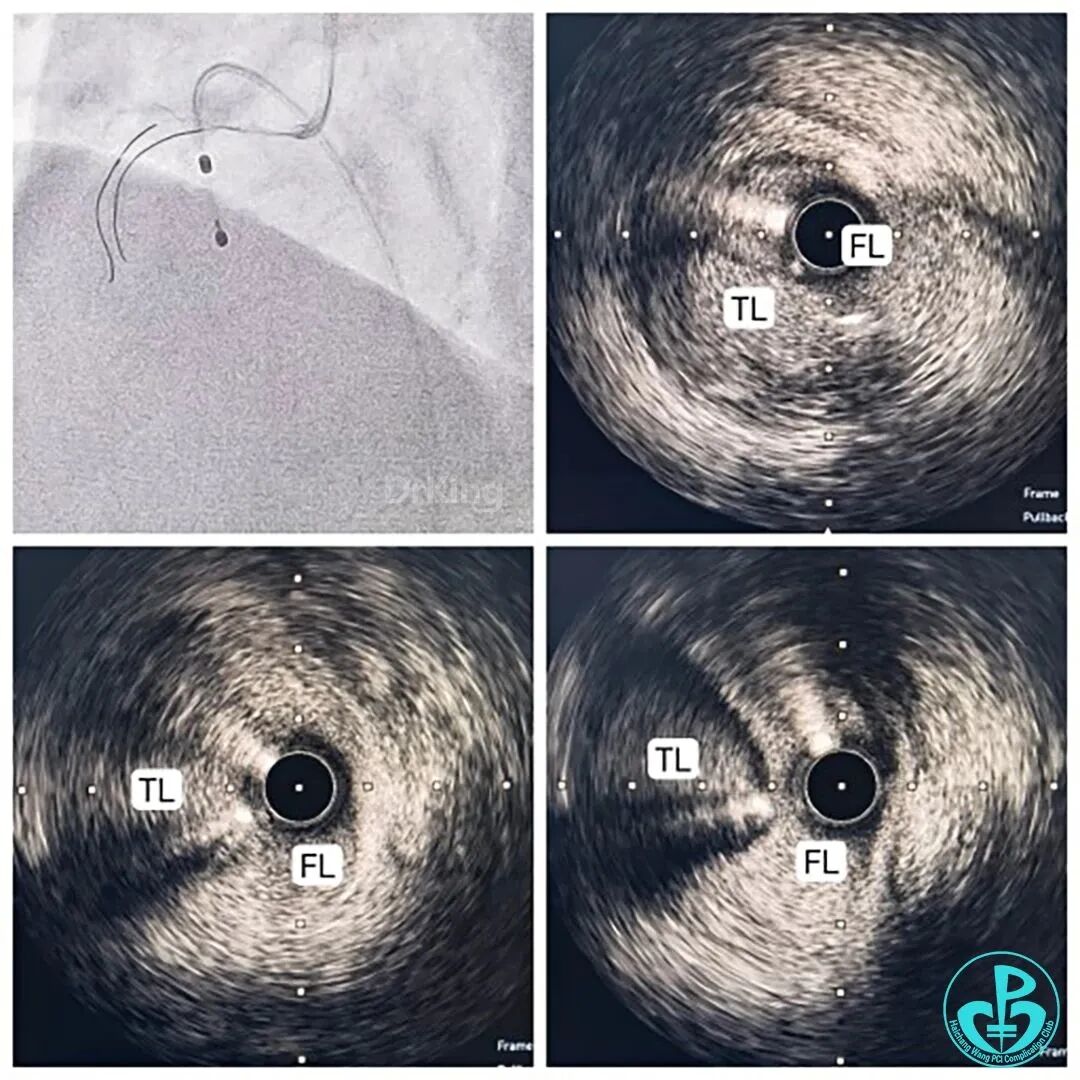

AL 1.0送至RCA口部,导引导丝未能送入,略回撤导引导管,压力曲线正常,轻冒烟见开口约5mm范围显影(用力较轻,未见造影剂向下游撕裂征象),天坑!夹层了!立即穿刺股静脉置入临时起搏器保护性起搏,换用JR 4.0导引导管,送入导丝至第一弯,行IVUS检查见RCA近开口处夹层,假腔巨大,真腔显著受压变小,期间患者胸痛、恶心、ST段抬高、心率血压下降,给予阿托品、去甲肾上腺素维持生命体征。

送入第二根导引导丝,在IVUS救急、实时指导&定位下(真腔3D定位于心包对侧,CAG对应IVUS标记点&第一根导丝下方),艰难操作,成功调进真腔内。